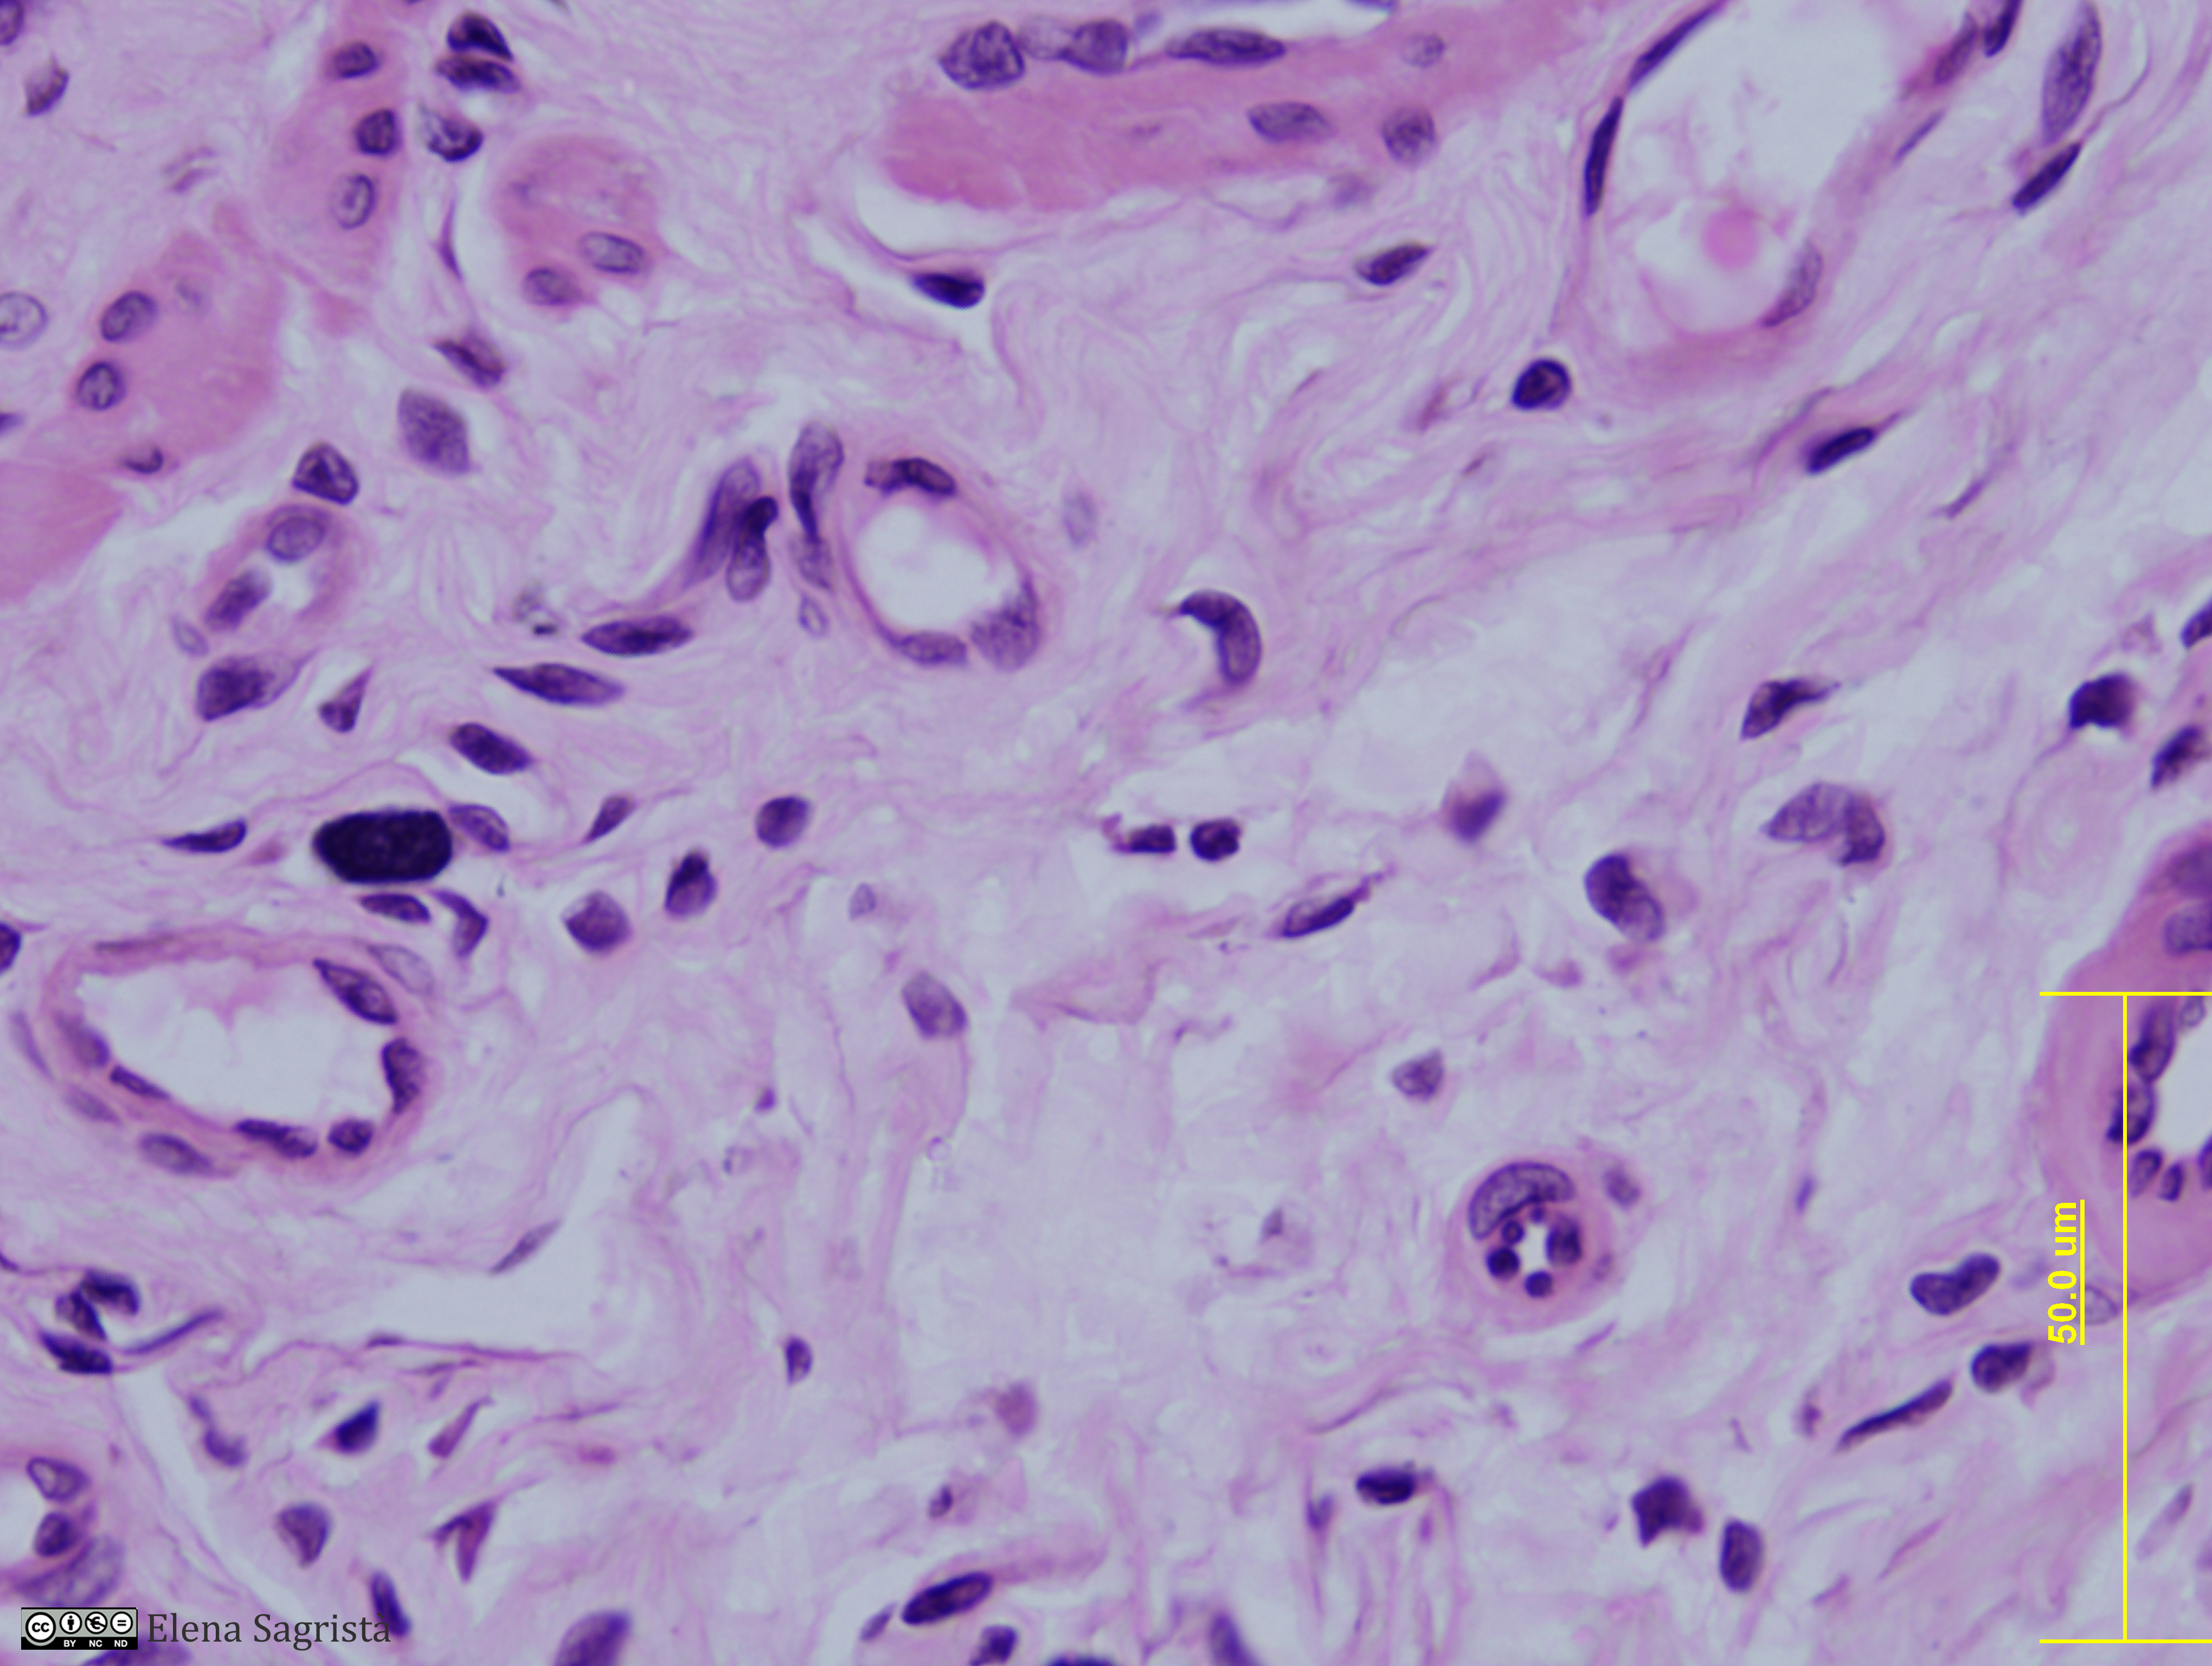

Histologia imatges: 15 Esòfag

| dc.description.abstract | Imatges de preparacions histològiques d'Esòfag. Microscopia òptica. | ca |

- 04 Teixit cojuntiu detall lamina propia esofag col·lagena capil·lars algun mastocit (HE).jpg